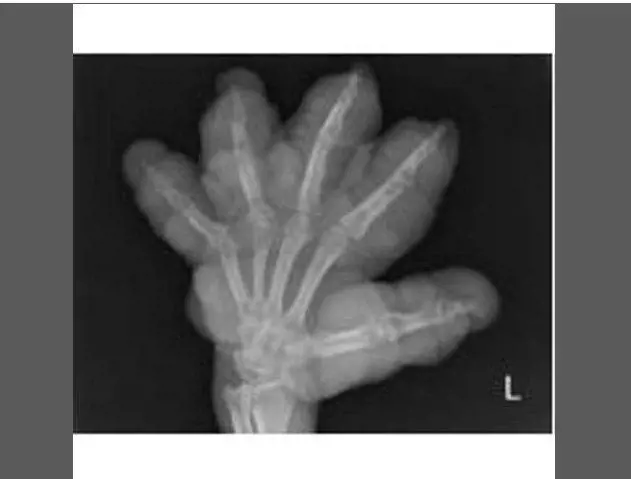

Pazze radiografie: gli oggetti che possono finire nel corpo umano

Oggetti bizzarri che hanno trovato la loro strada all'interno del corpo umano, e documentati grazie alle pazze radiografie raccolte dal dottor Frank Gaillard. Quest’ultimo ha fondato Radiopaedia.org, un sito collaborativo che raccoglie casi radiologici e articoli medici a tema.